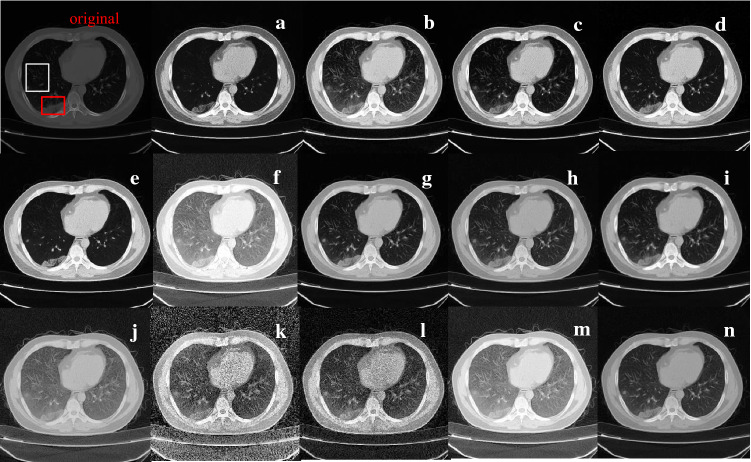

While professional radiologists are trained to read the standard CT scans, the accuracy of diagnosis and the time taken for it can be optimized by using the images of better visual quality. Typical examples of enhanced images using 14 techniques used in this study are shown in Fig. 1. We applied the six above-mentioned metrics to all 50 sets of enhanced images and calculated the average scores of each technique as shown in Table 2. Based on these average scores a rank between 1 and 14 is assigned to each technique by each metric as shown in Table 3.

Fig. 1.

Experimental results of different Image enhancement techniques a BBHE b DSIHE c MMBEBHE d RMSHE e RSIHE f RSWHE g AGCWD h ESIHE i R-ESIHE j RS-ESIHE k BHE l cl-BHE m PQ n NLQ

Comparing the rankings given by the metrics with those given by the radiologists, we did not observe a good correlation between the two. Three metrics, Entropy, EME, and EMEE, rank technique (k) BHE as the best, whereas it was at the last position in radiologist’s ranking. In fact, out of 50 images, each enhanced by 14 techniques, not even one enhanced by BHE was picked as the best by the radiologists. The other three metrics SSIM, PSNR, and AMBE kept (d) RMSHE at the first position which stood at 5th position in radiologist’s ranking. We discussed these results with the radiologists and based on their feedback, the ground-glass opacities are soft tissues, which are the regions of their interest for COVID-diagnosis. We have marked these regions with white and red boxes in the original image shown in Fig. 1. The methods that enhance these regions are ranked high by the radiologists. Looking at the example of RMSHE discussed above, it enhances the details in some parts at the expense of other regions. In case of COVID-19 images, the suppressed regions by RMSHE happen to be of radiologist’s interest. Therefore, neither this technique, not the three metrics that prefer it are a good choice for the COVID-19 CT images.

Top 3 techniques ranked by the radiologist as well as the combined evaluation by the metrics are techniques (i) R-ESIHE, (g) AGCWD, and (n) NLQ. We can observe good uniform enhancement in each region of the resultant images generated by these techniques, including the regions of interest marked by the red and white rectangles in the original image in Fig. 1. Technique (b), which was among top 3 picks of the radiologist but was not picked by the metric, also shows very good enhancement.

The worst performing techniques, as per the radiologist were (k) BHE, (a) BBHE, and (j) RS-ESIHE. If we look at the sample images produced by these techniques in Fig. 1, we can note that (k) BHE shows less enhancement in the regions of interest marked by the radiologists but enhances the noise in other parts. This is the reason it was picked as the best by the metrics that rely on the enhancement of details and contrast – entropy, EME, and EMEE. This shows that the higher values of detail and contrast metrics in medical imaging may be due to higher noise presence, and therefore they should be used with caution. In Fig. 1 if we look at the sample image of (a) BBHE, we can see that the enhancement in the region of ground-glass opacities is less as compared to other images and the region surrounding the soft tissues is also suppressed. The technique (j) RS-ESIHE does not seem to lose details; however, the enhancement in all regions is mediocre.